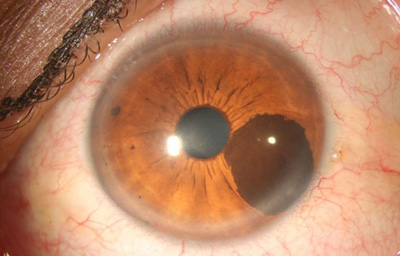

Nevus melanociticos en el Iris

Archivo Fotográfico Dr. Francisco Barraquer

Nevus melanociticos en el Iris

Archivo Fotográfico Dr. Francisco Barraquer

Nevus con escaso pigmento

Archivo Fotográfico Dr. Francisco Barraquer

Se considera que los adquiridos son neoplasmas benignos, mientras que los congénitos (perinatales) son considerados con un mayor riesgo de malignización.

Son mas frecuentes en Iris claros, y su crecimiento o riesgo de malignización, esta relacionado con la edad siendo más frecuente en gente joven;

Shields (28) creó una guía con letras: ABCDEF para recordar los factores de riesgo predictivos de malignización:

A = ( Age) edad joven

B = (Blood) vascularización

C = (Clock hour inferior) localización inferior

D = (Diffuse config) configuración difusa

E = Ectropion

F = (Feathery margin) margen plumoso

Esas características clínicas, ayudan a identificar un Melanoma del Iris vs un Nevus a tiempo, o en una etapa en la que el tratamiento pueda salvar la vida.